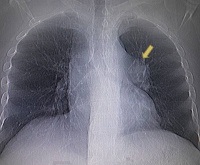

• Лучевая диагностика. Рентгенографическое изображение зависит от расположения аневризматического мешка. С расширением ствола или его левой ветви рентгенограммы OGCs определяют округлое образование в области левого корня. Аневризма правой ветви проявляется увеличением поперечного сечения артерии в виде запятой, расположенной в области правого корня. Патология периферических сосудов представлена плотными, однократными или множественными округлыми тенями. Ангиопульмонография позволяет уточнить месторасположение процесса.

КТ ангиография кровеносных сосудов сердца. Местное аневризматическое расширение ветви правой легочной артерии.